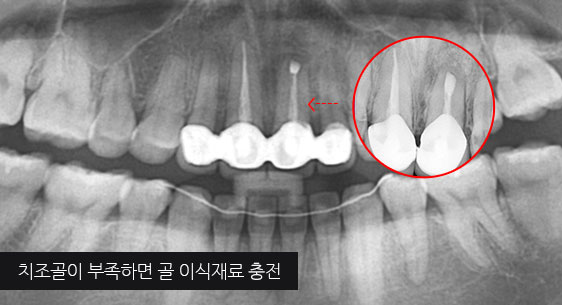

심한 염증으로 치조골이 광범위하게 소실, 아래쪽 신경관이 가까이 있어 치근단수술이 불가능한 상태, 타 병원에서 임플란트 진단을 받았지만,

고운미소치과에서 치아를 발치하고 뿌리 쪽 염증을 제거한 후 발치한 치아를 다시 심는 치아재식술을 시행하였습니다.

기존 신경치료 부위에 염증과 치조골이 소실되고 있는 상태

치아를 발치하고 염증을 제거, MTA로 충전하고 치아를 다시 심음. (난이도 최상)